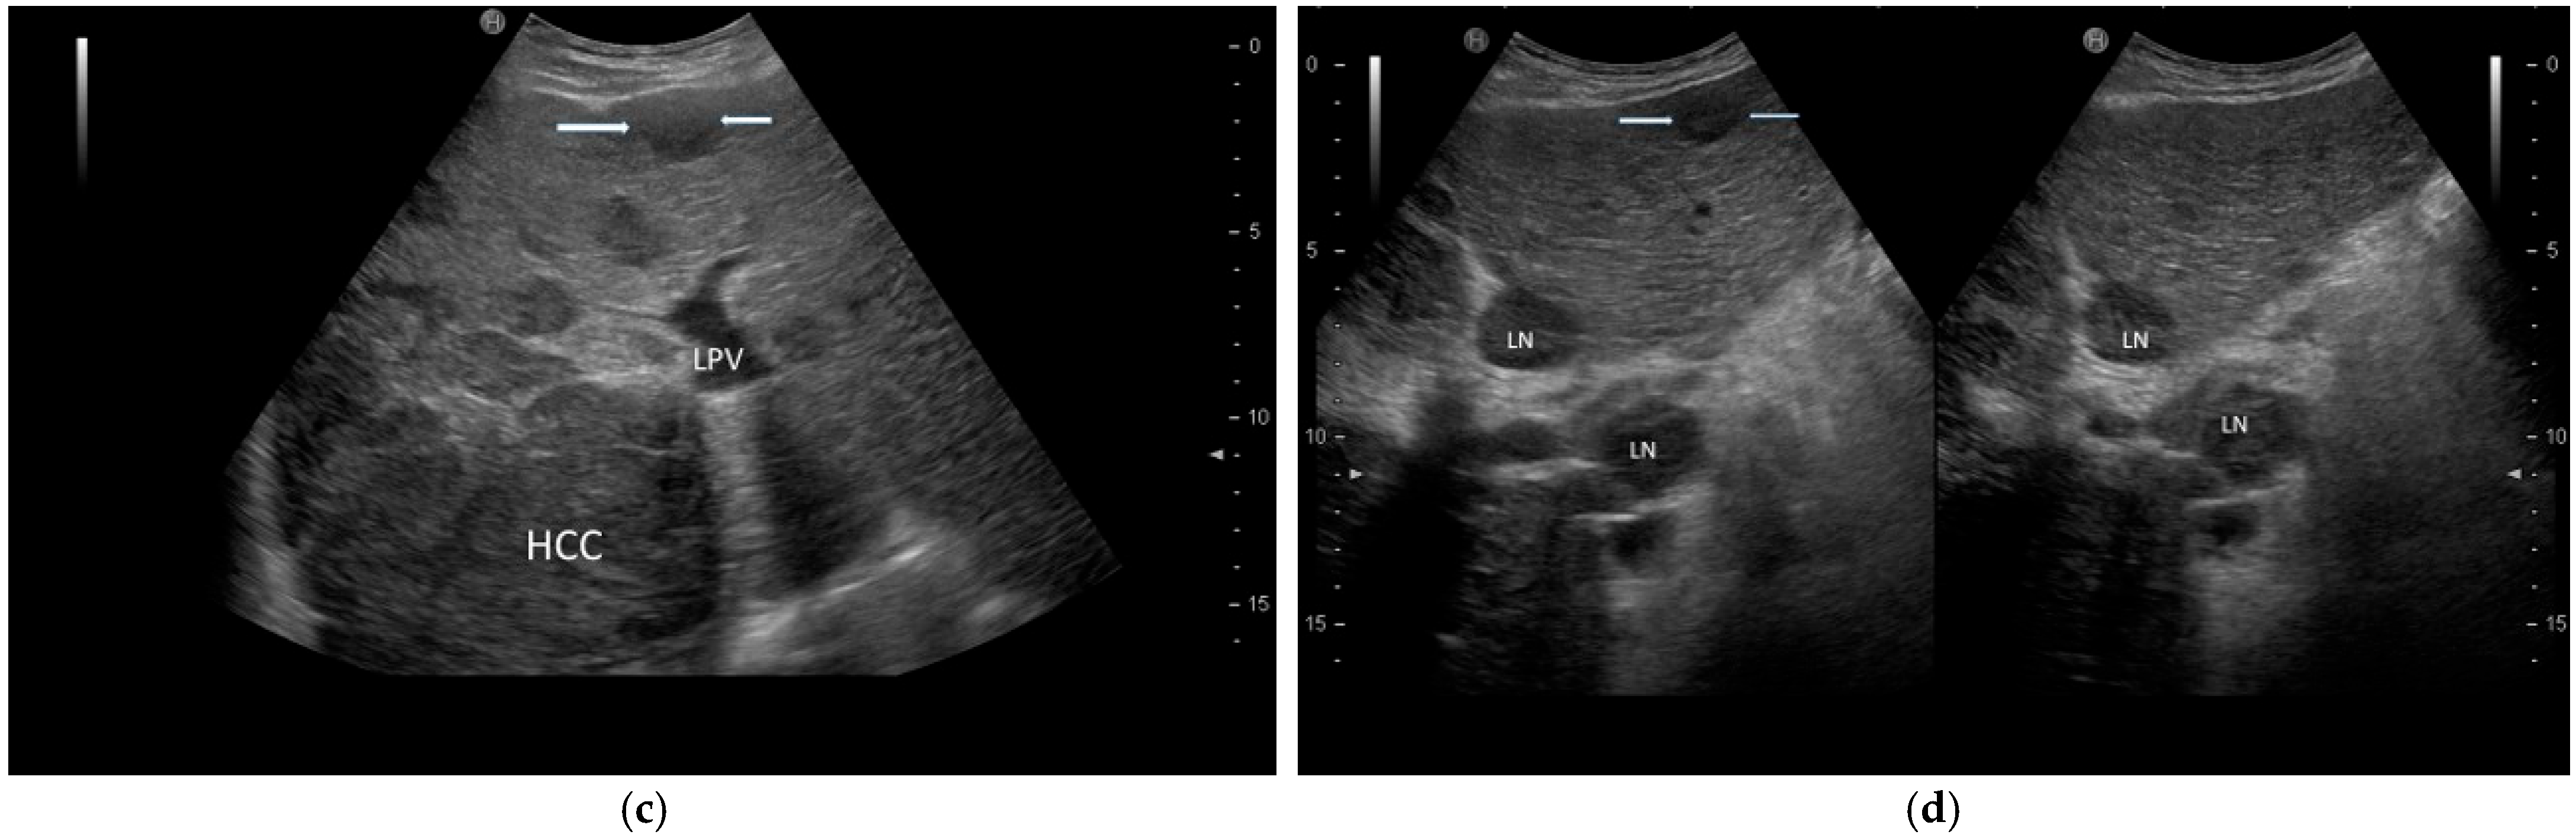

| POST-VIRAL HCC | MASLD HCC |

|---|---|

|

| |

| These characteristics would be focused more on the lack of malignancy rather than HCC. | |